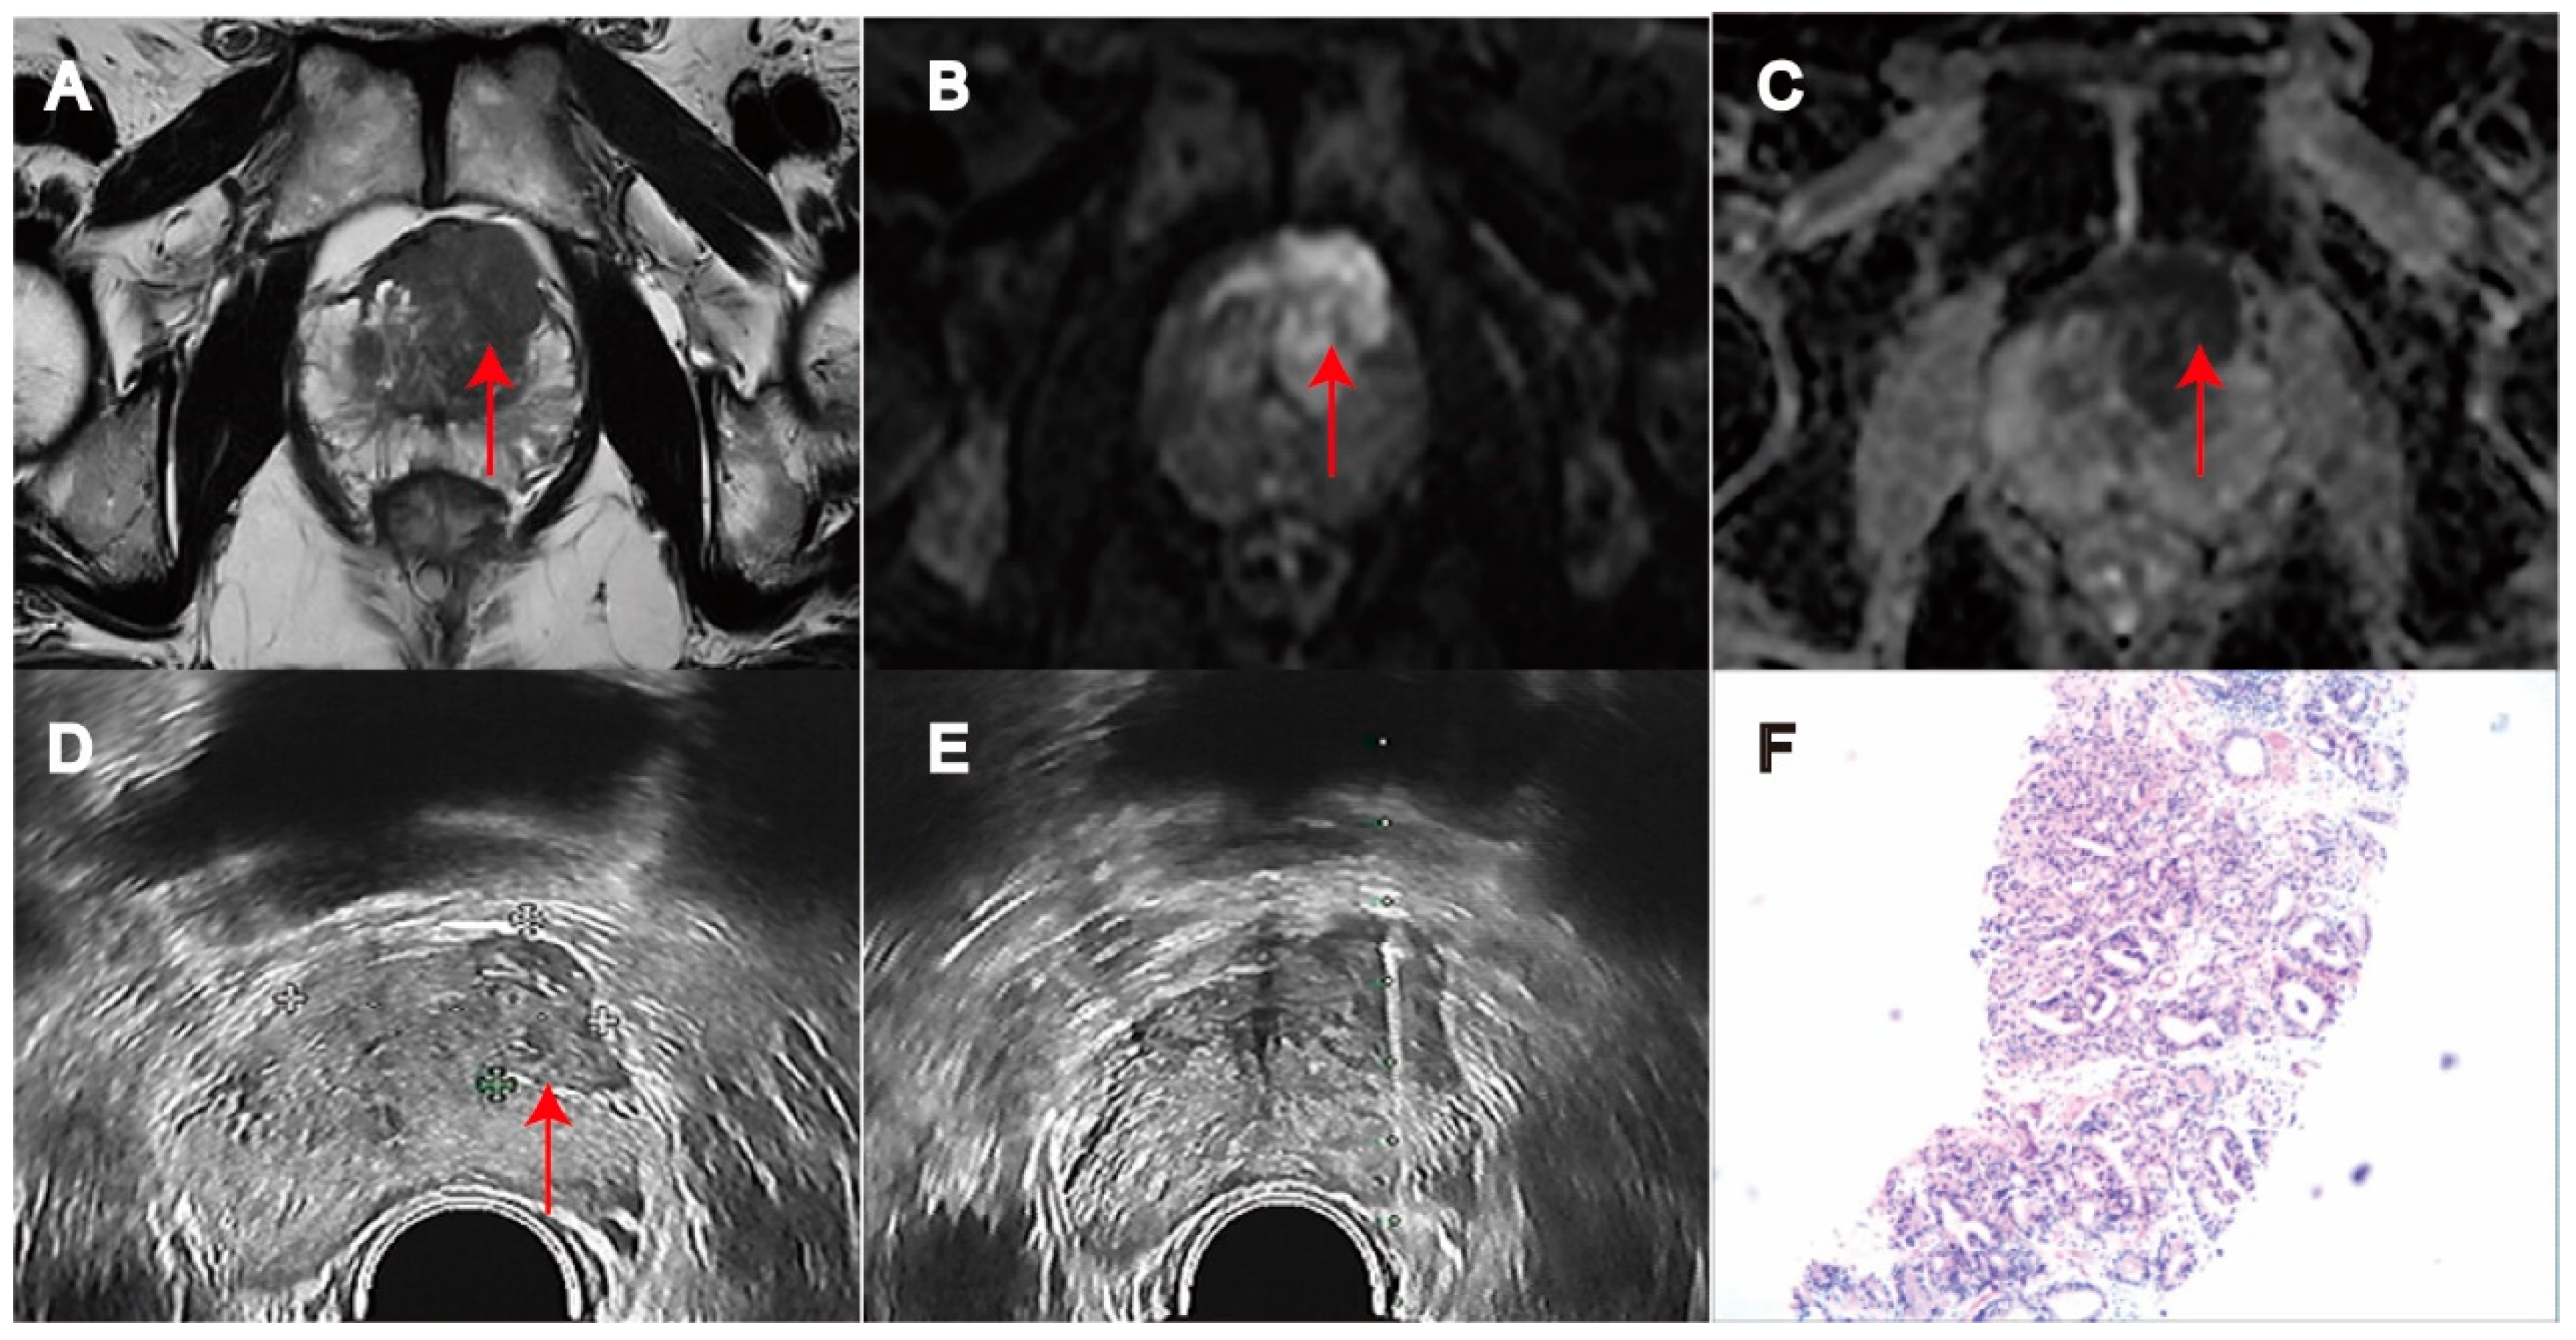

Comparison of Targeted Biopsy and Combined Biopsy to Avoid Unnecessary Systematic Biopsy in Patients with PI-RADS 5 Lesions

2. Materials and Methods

2.3. Prostate Biopsy